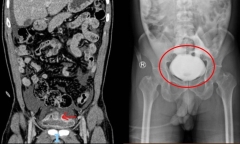

Bệnh viện Quân y 175 (TP.HCM) vừa phẫu thuật cấp cứu, bảo tồn thành công cơ quan sinh sản cho một nam sinh viên 21 tuổi bị xoắn tinh hoàn.

Nhịn tiểu khi uống bia, một người đàn ông đã bị vỡ bàng quang, được các y bác sĩ Bệnh viện Nhân dân 115 kịp thời cứu chữa.